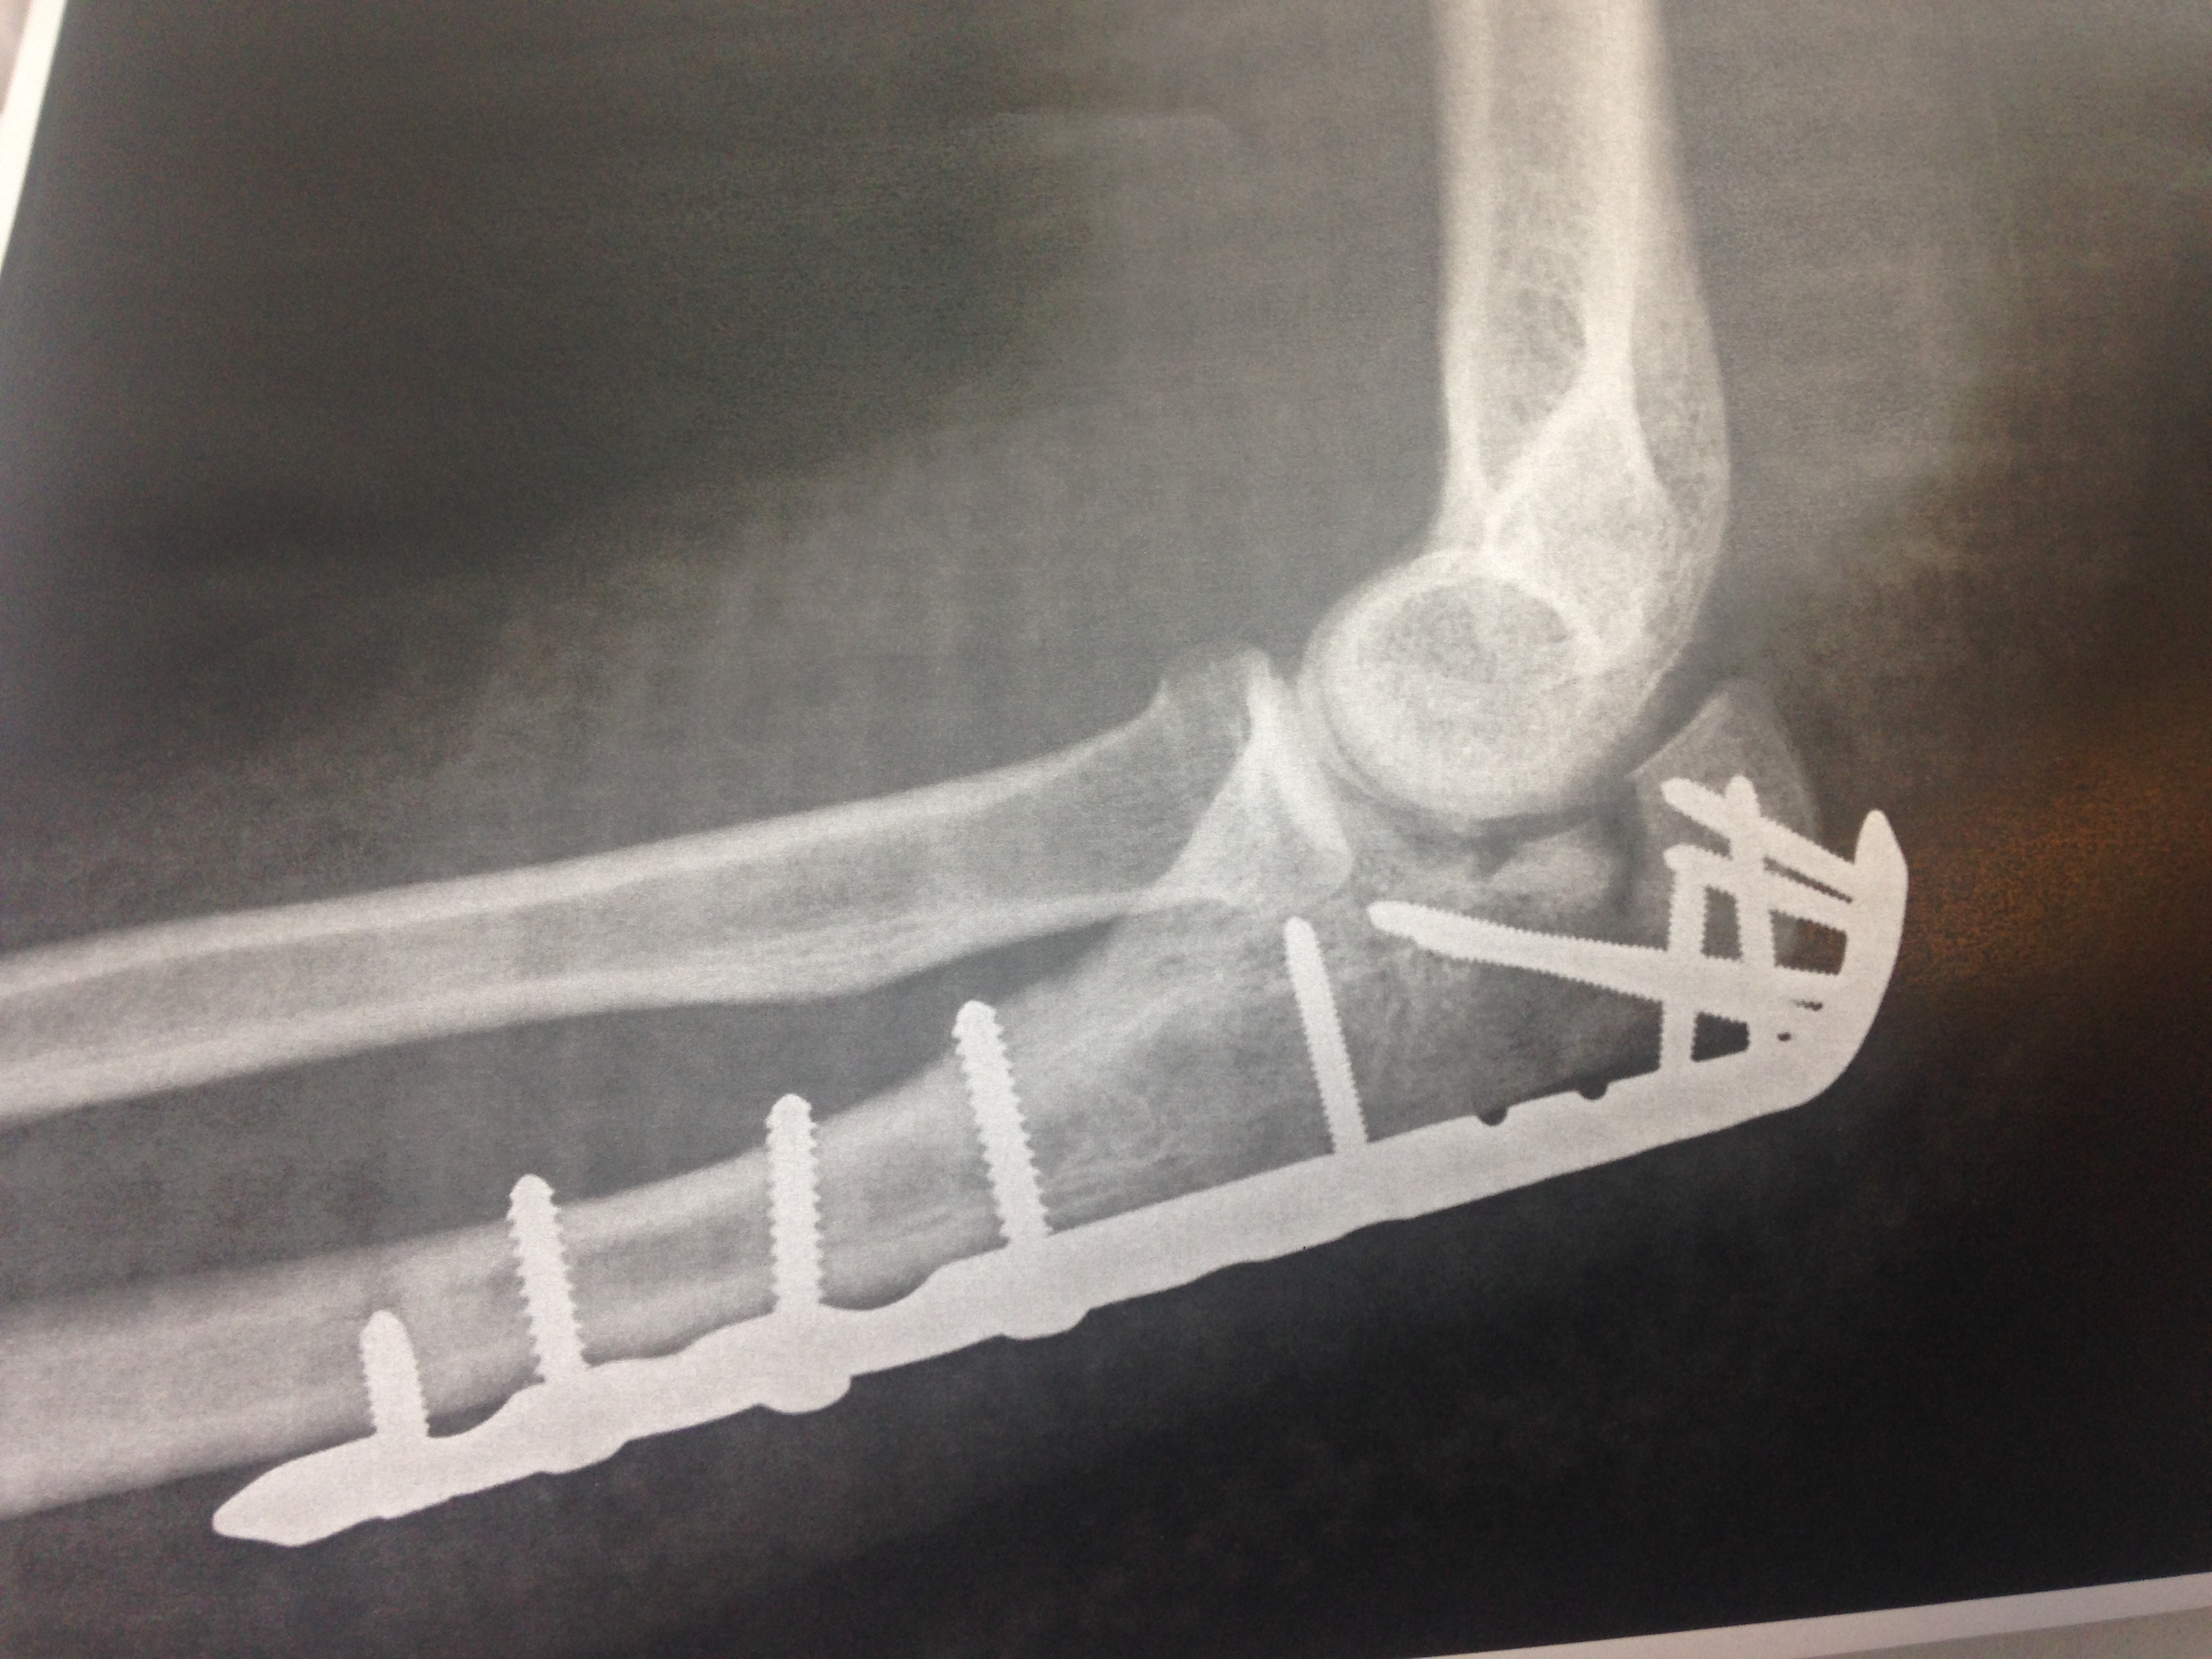

Efter operation

- Røntgenbilledet viser, hvordan man har sat skruer og metalplade i albueknoglen for at holde et forskudt brud på olecranon sammen.

- Det ser voldsomt ud, men det gør ikke ondt at have skruerne og pladen siddende, og efter et stykke tid med ro kan man begynde at genoptræne albuen.

- Plade og skruer kan blive siddende i knoglen for altid, men er de til gene, er det muligt at fjerne dem efter et år, når knoglen er solidt helet.

- På albuebenet generer pladen let, da den sidder lige under huden, så der er der ofte brug for at pladen og skruerne fjernes ved en ny operation.